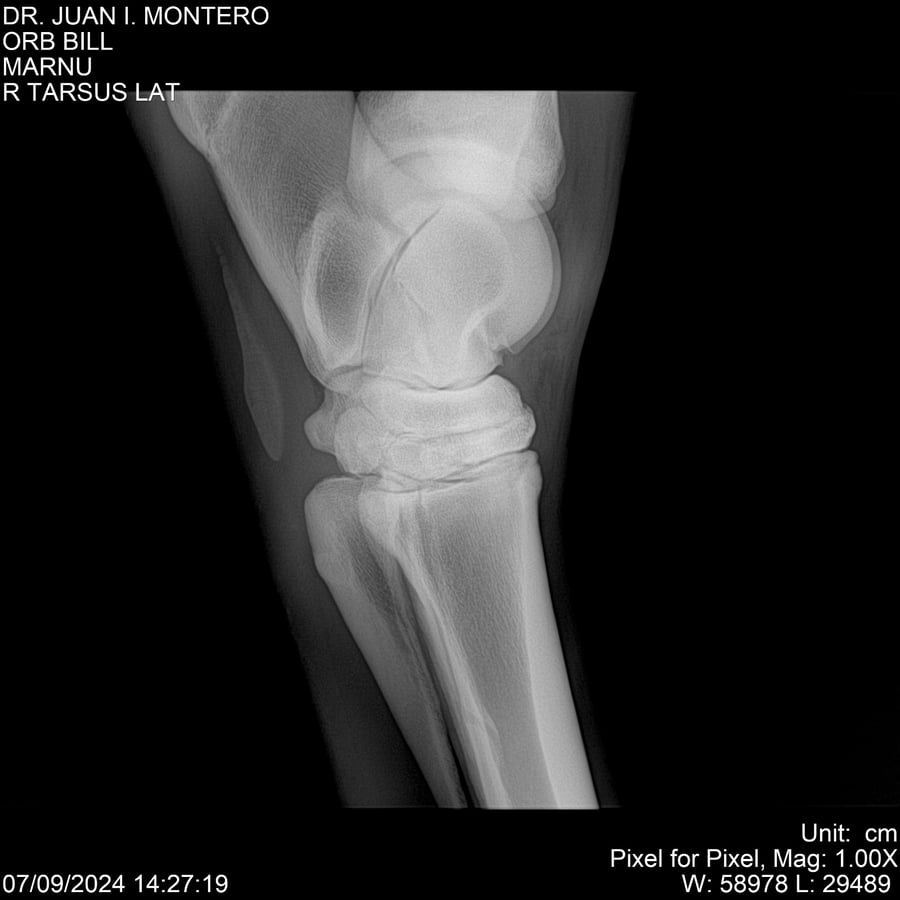

LOTE 7, ORB BILL 🔥 🔥 🔥 Lote Anterior Volver al remate Lote Siguiente Ficha Contacto Montevideo - Ficha del Lote Identificador: #282523 Categoría: Yeguarizos Montevideo - 83 Visualizaciones ClicData Contacto Empresa: Abelenda N. R., Walter Hugo Nombre*: Teléfono* : E-mail* : Mensaje Enviar Registrese gratis Este contenido Exclusivo está disponible sólo para usuarios registrados Ingresar